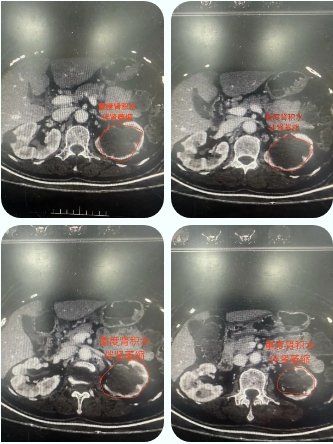

近日,近3年未曾查体及复查的患者因“低热伴无法进食1月”来到青岛西海岸新区中医医院治疗。入院后完善CT检查显示“左输尿管下段长约4cm结石石阶,左肾内多发结石,左肾重度积水伴肾萎缩”。

由于孔大叔多次行经皮肾镜、输尿管软镜手术及长期重度肾积水并感染导致肾包膜与肾周脂肪组织及腹膜粘连严重,术中分离难度极大,容易出血。肾萎缩导致肾脏大量脂肪堆积,肾动脉静脉变细,分离血管难度大。

术中,汤方旺副主任医师通过3D腹腔镜系统放大视野,精准锐性分离肾周组织,针对肾门血管复杂粘连,采用先分离出肾脏,将肾门血管集束夹闭离断,完整切除患肾,避免损伤周围血管及脏器。